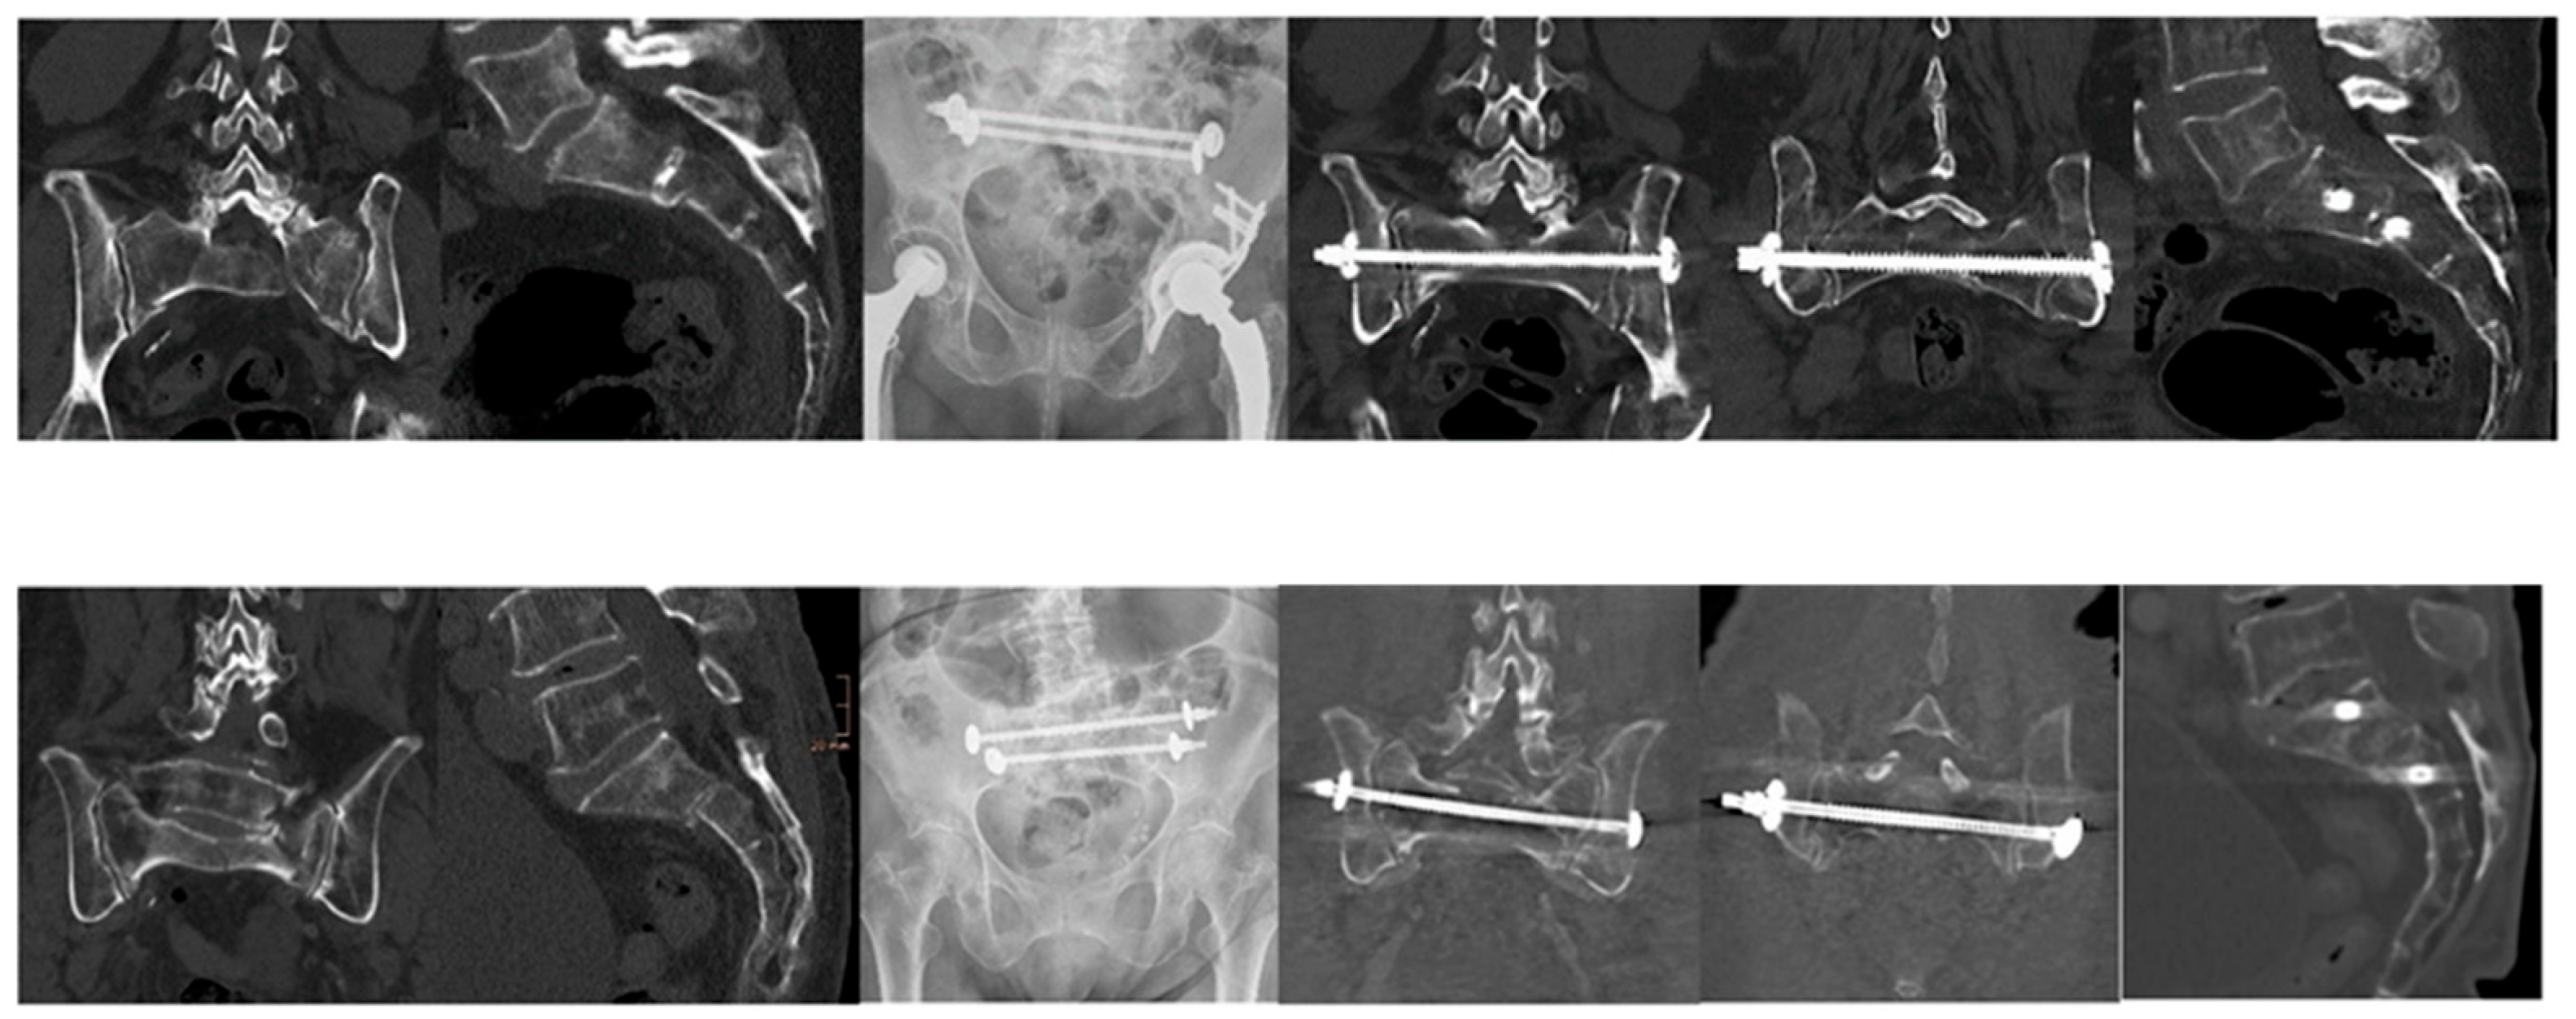

- Hybrid construct (TSB + bilateral iliosacral screws): A cannulated TSB (7.5 mm) was inserted percutaneously across the sacral body (typically S1) under navigated control. Two partially threaded iliosacral screws were then inserted bilaterally, usually at S1 but occasionally at S2 if anatomy dictated.

- Dual-bar construct (two parallel TSBs): In cases with adequate screw corridors or poor bone purchase, two parallel bars were introduced (S1 and S2). This configuration increased torsional resistance while maintaining a minimally invasive profile.